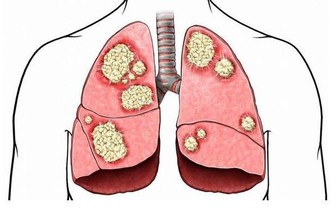

“嫌貧愛富”,我們常用來形容對人的好惡以其貧富為準。但有一種癌症,它也具有這種特性,那便是大腸癌。

大腸癌是與飲食習慣密切相關的疾病,隨著經濟水平提高,生活富裕,食物越多,吃得越好,大腸癌也變得越“活躍”。在我國,每年有14萬人被確診患大腸癌,而且發病率每年遞增2.5%~5.0%,遠遠高於全球平均水平的2%。

如何才能避免大腸癌找上門?關鍵還得從改變飲食習慣開始。